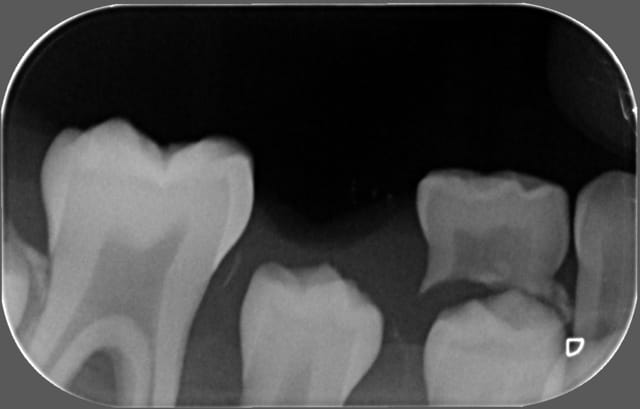

abcès important en regard de la 84, j'extrais ce jour la dent,mais comme je n'ai pas pu avoir une bonne rétro,je fais une pano,

est-ce qu'il y a une image au niveau de la 46 ?

problème au niveau de l'apex de 45 ?

en gros l'abcès (évolution en cellulite) peut-il être du à un problème sur 44 , 45 ou 46 ?

je pense vraiment que les lésions à l'apex de 44, 45 et 46 sont juste l'image de la formation des apexs et que cela n'a rien à voir avec une image infectieuse. Surtout, d'où serait venu les bactéries?

La 45 est bizarre, on dirait que la racine n'a quasiment pas été formée alors qu'elle n'est pas si profonde.

La radioclarté autour de 45 est douteuse.

Franchement, je ne vois pas en quoi 44 45 46 pourraient être mises en causes et l'apparence de radioclarté me semble plus liée à une ligne dense continue qui se prolonge en région symphysaire et qui s'apparente à un artéfact cinétique de la pano.

Ce serait quand même surprenant que sur les 2 panos il y ait eu un artéfact exactement au même endroit, et à l'endroit où on suspecte quelque chose.

il semble que l'absence de formation radiculaire de la 45 peut être due à la perte précoce de la 85

La 85 était très moche, c'est la porte d'entrée la plus évidente, qui a dû perturber l'évolution de 45.

quelques idéees à mon amha!je pense que le problème vient des apex de la 46!!!

J'ai eu une patiente de 14 ans avec un genre de foyer/kyste

aux apex d'une 47 parfaitement vivante.J'ai demandé un avis d'une endodontiste exclusive qui m'a confirmé un kyste apicale du sans doute à une évolution non logique lors de l'apexification(peut etre évolution de la gaine D'Hetwig non conforme)Résultat curetage

La cellulite se transmet au travers de la joue à partir de 46

je ne vois pas la 84 responsable ni la 44 et 45 en évolution